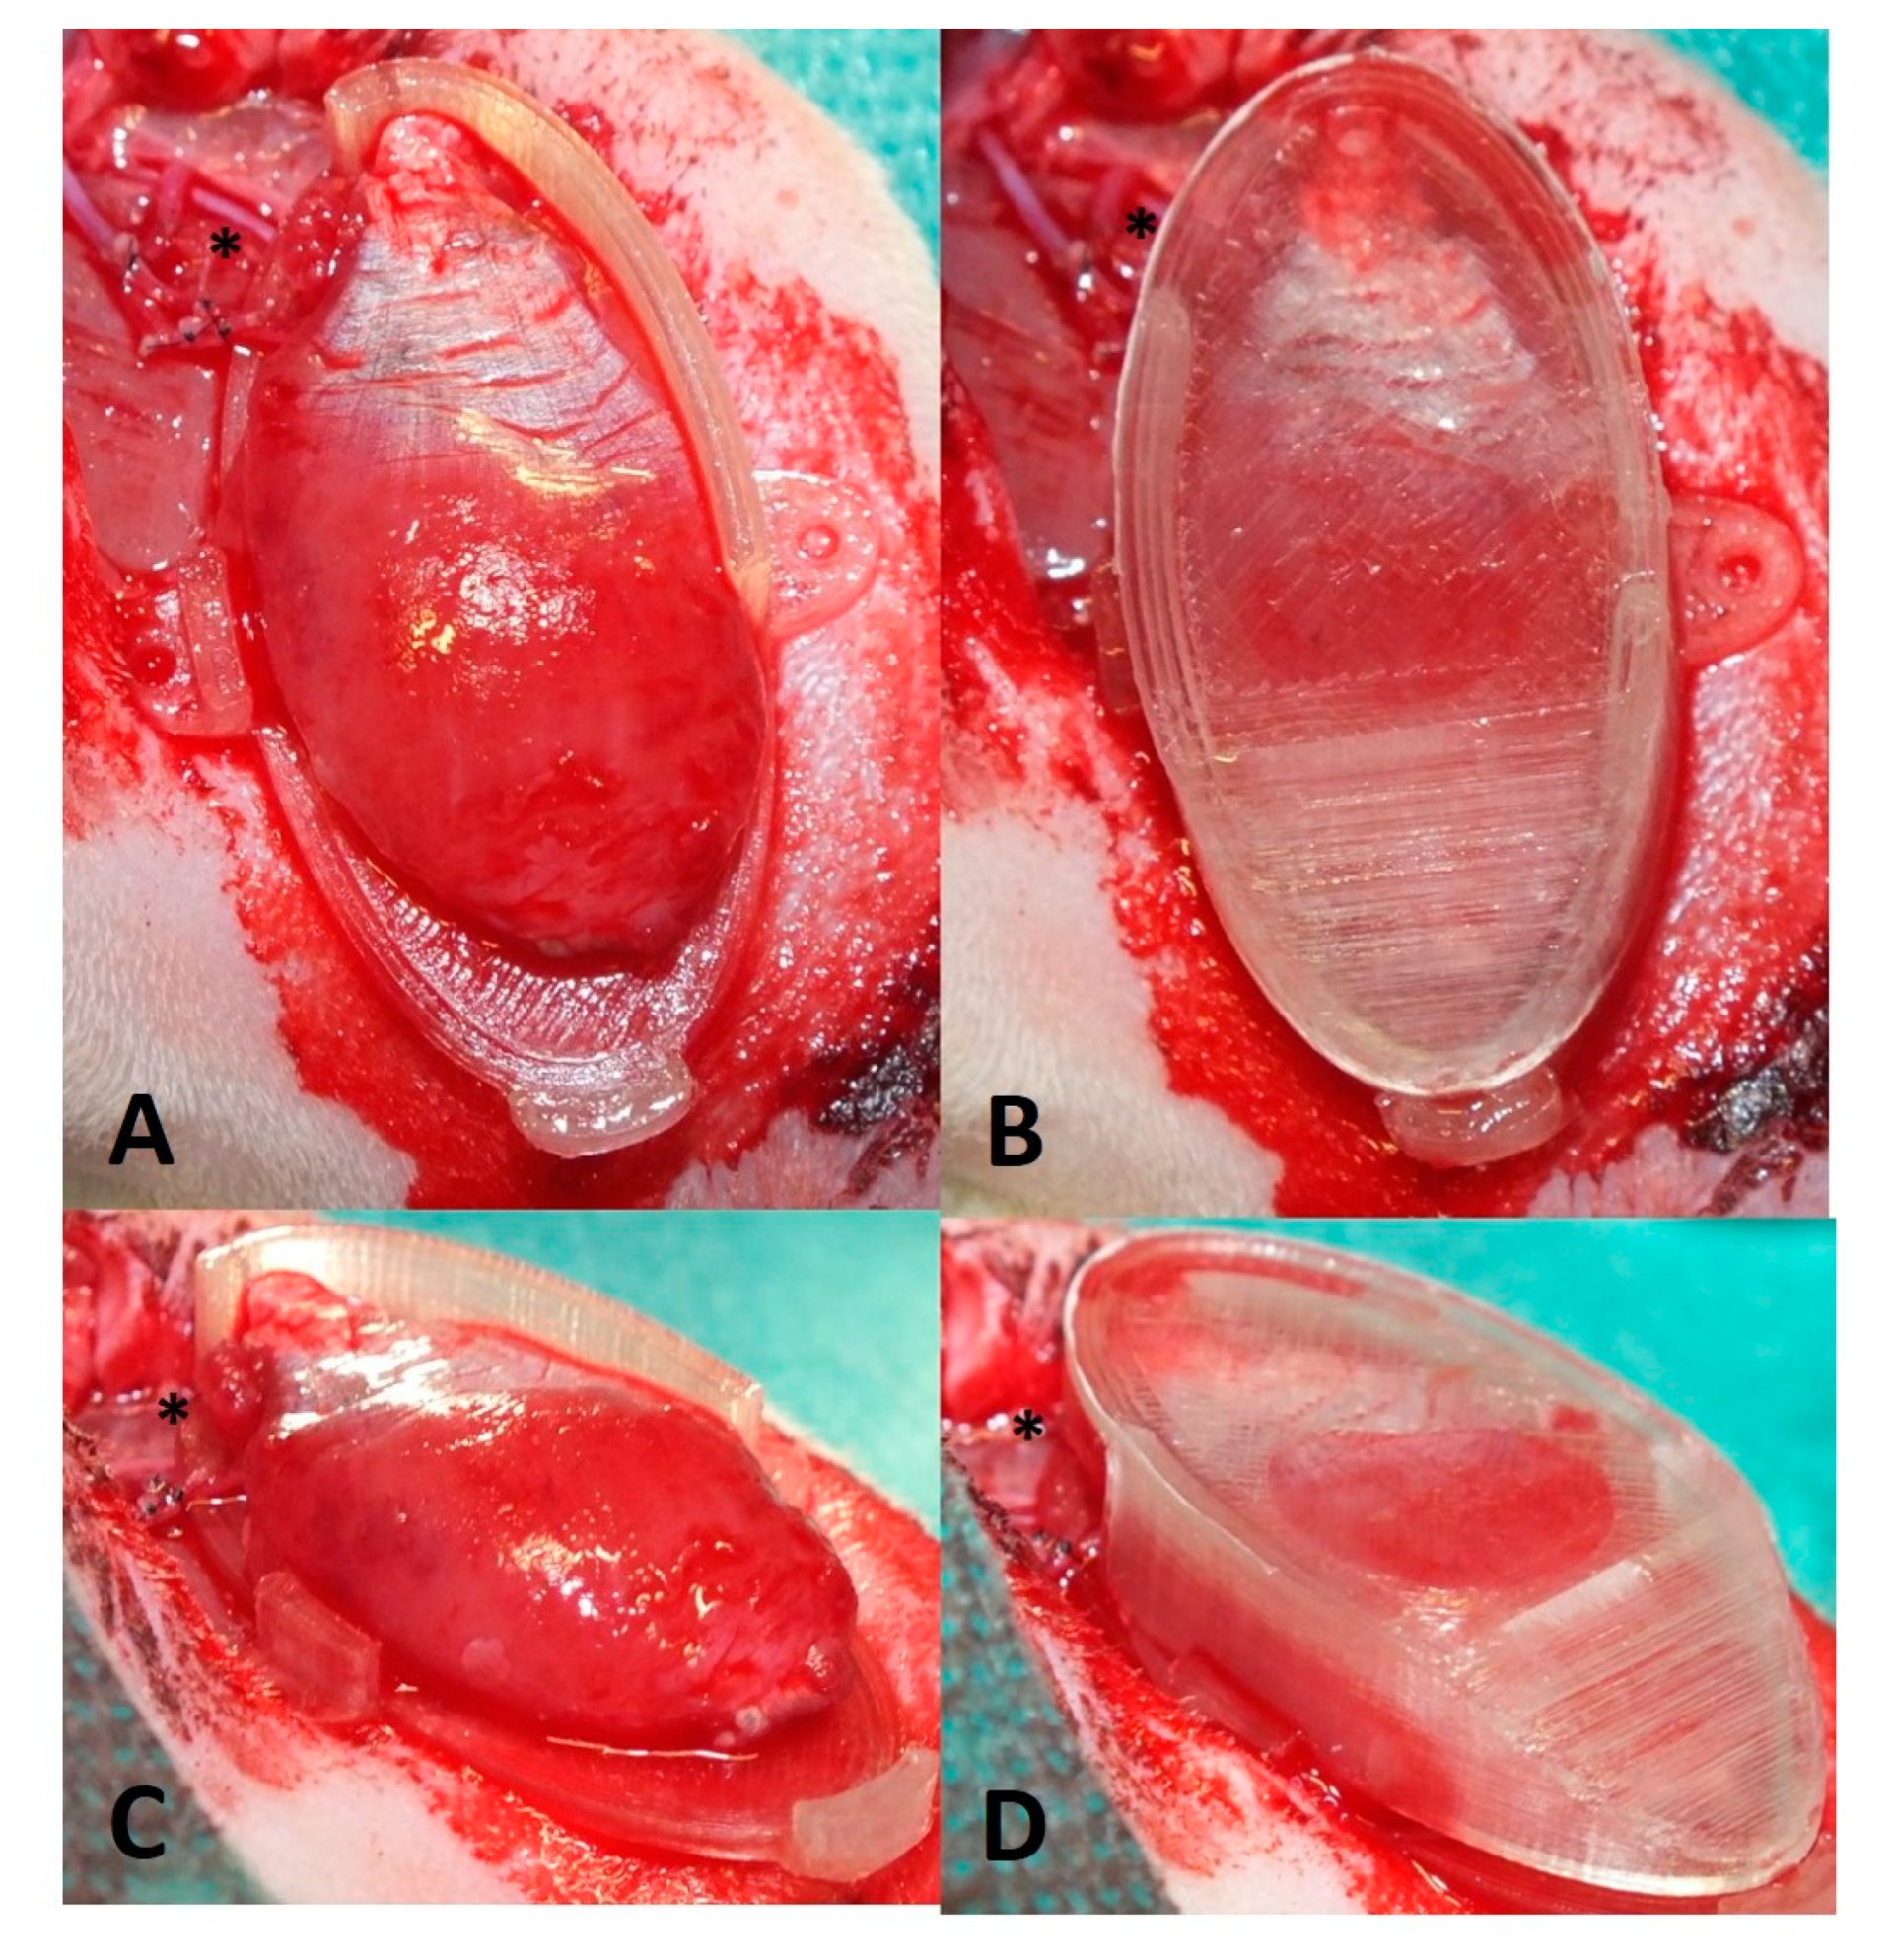

2.5. Perfusion and Explantation of Constructs

3.1. Surgery and Animals